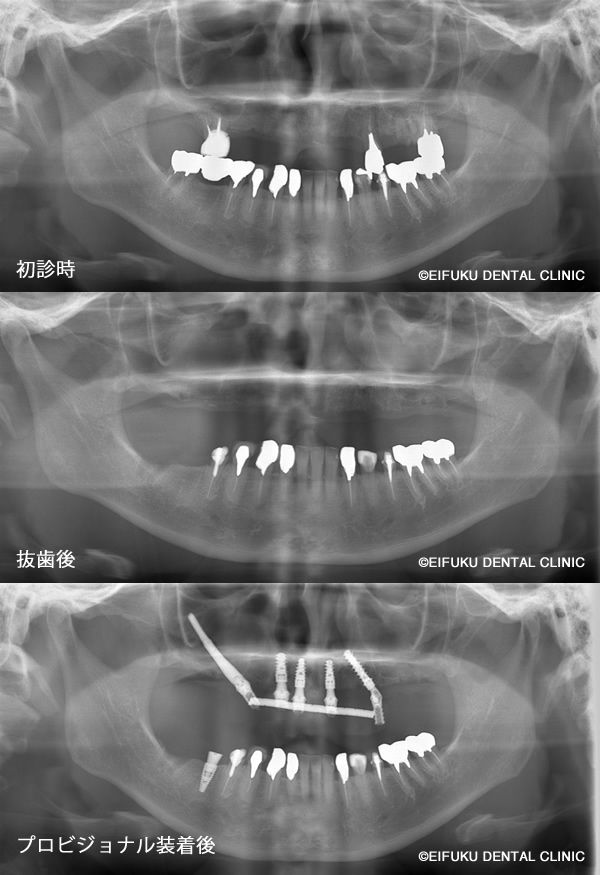

| コメント | 40代の男性、患者さんは、「歯が動いてしっかり噛めない」「歯ぐきから血が出る」「歯が割れてしまった」というお悩みで来院されました。 重度の歯周病と歯の破折が進行しており、上顎の多くの歯は保存が難しく、このままでは仕事や日常生活に支障が出るほど噛む力が低下している状態でした。「とにかく早く噛めるようになりたい」「総入れ歯にはしたくない」という患者さんのご希望から、上顎は左右の頬骨にインプラントを固定するザイゴマインプラントを用いたオールオン形式の治療計画を立案しました。 通常のオールオン4では骨量が不足しているケースでも、頬骨を利用することで強固な固定が得られ、ブリッジ状の固定式の歯を支えることが可能になります。精密検査のうえ、残存歯を抜歯しながら同時にザイゴマインプラントを埋入し、十分な初期固定を確認したうえで、その日のうちに固定式の仮歯を装着しました。術後まもなく柔らかい食事から再開でき、「ぐらぐらせずしっかり噛める」「人前で思い切り笑えるようになった」と大変喜んでいただけました。ザイゴマインプラントを用いたオールオン形式は、歯がボロボロで動いている、歯ぐきから血が出る、歯が割れて噛めないなど重度の症状でも、短期間でしっかり噛める状態を目指せる治療オプションです。 当院では、骨量不足や重度歯周病でお悩みの方に対しても、専門的なインプラント治療と丁寧なカウンセリングで、早期に「噛める」「見た目も回復する」ことを重視した治療をご提案しています。 |